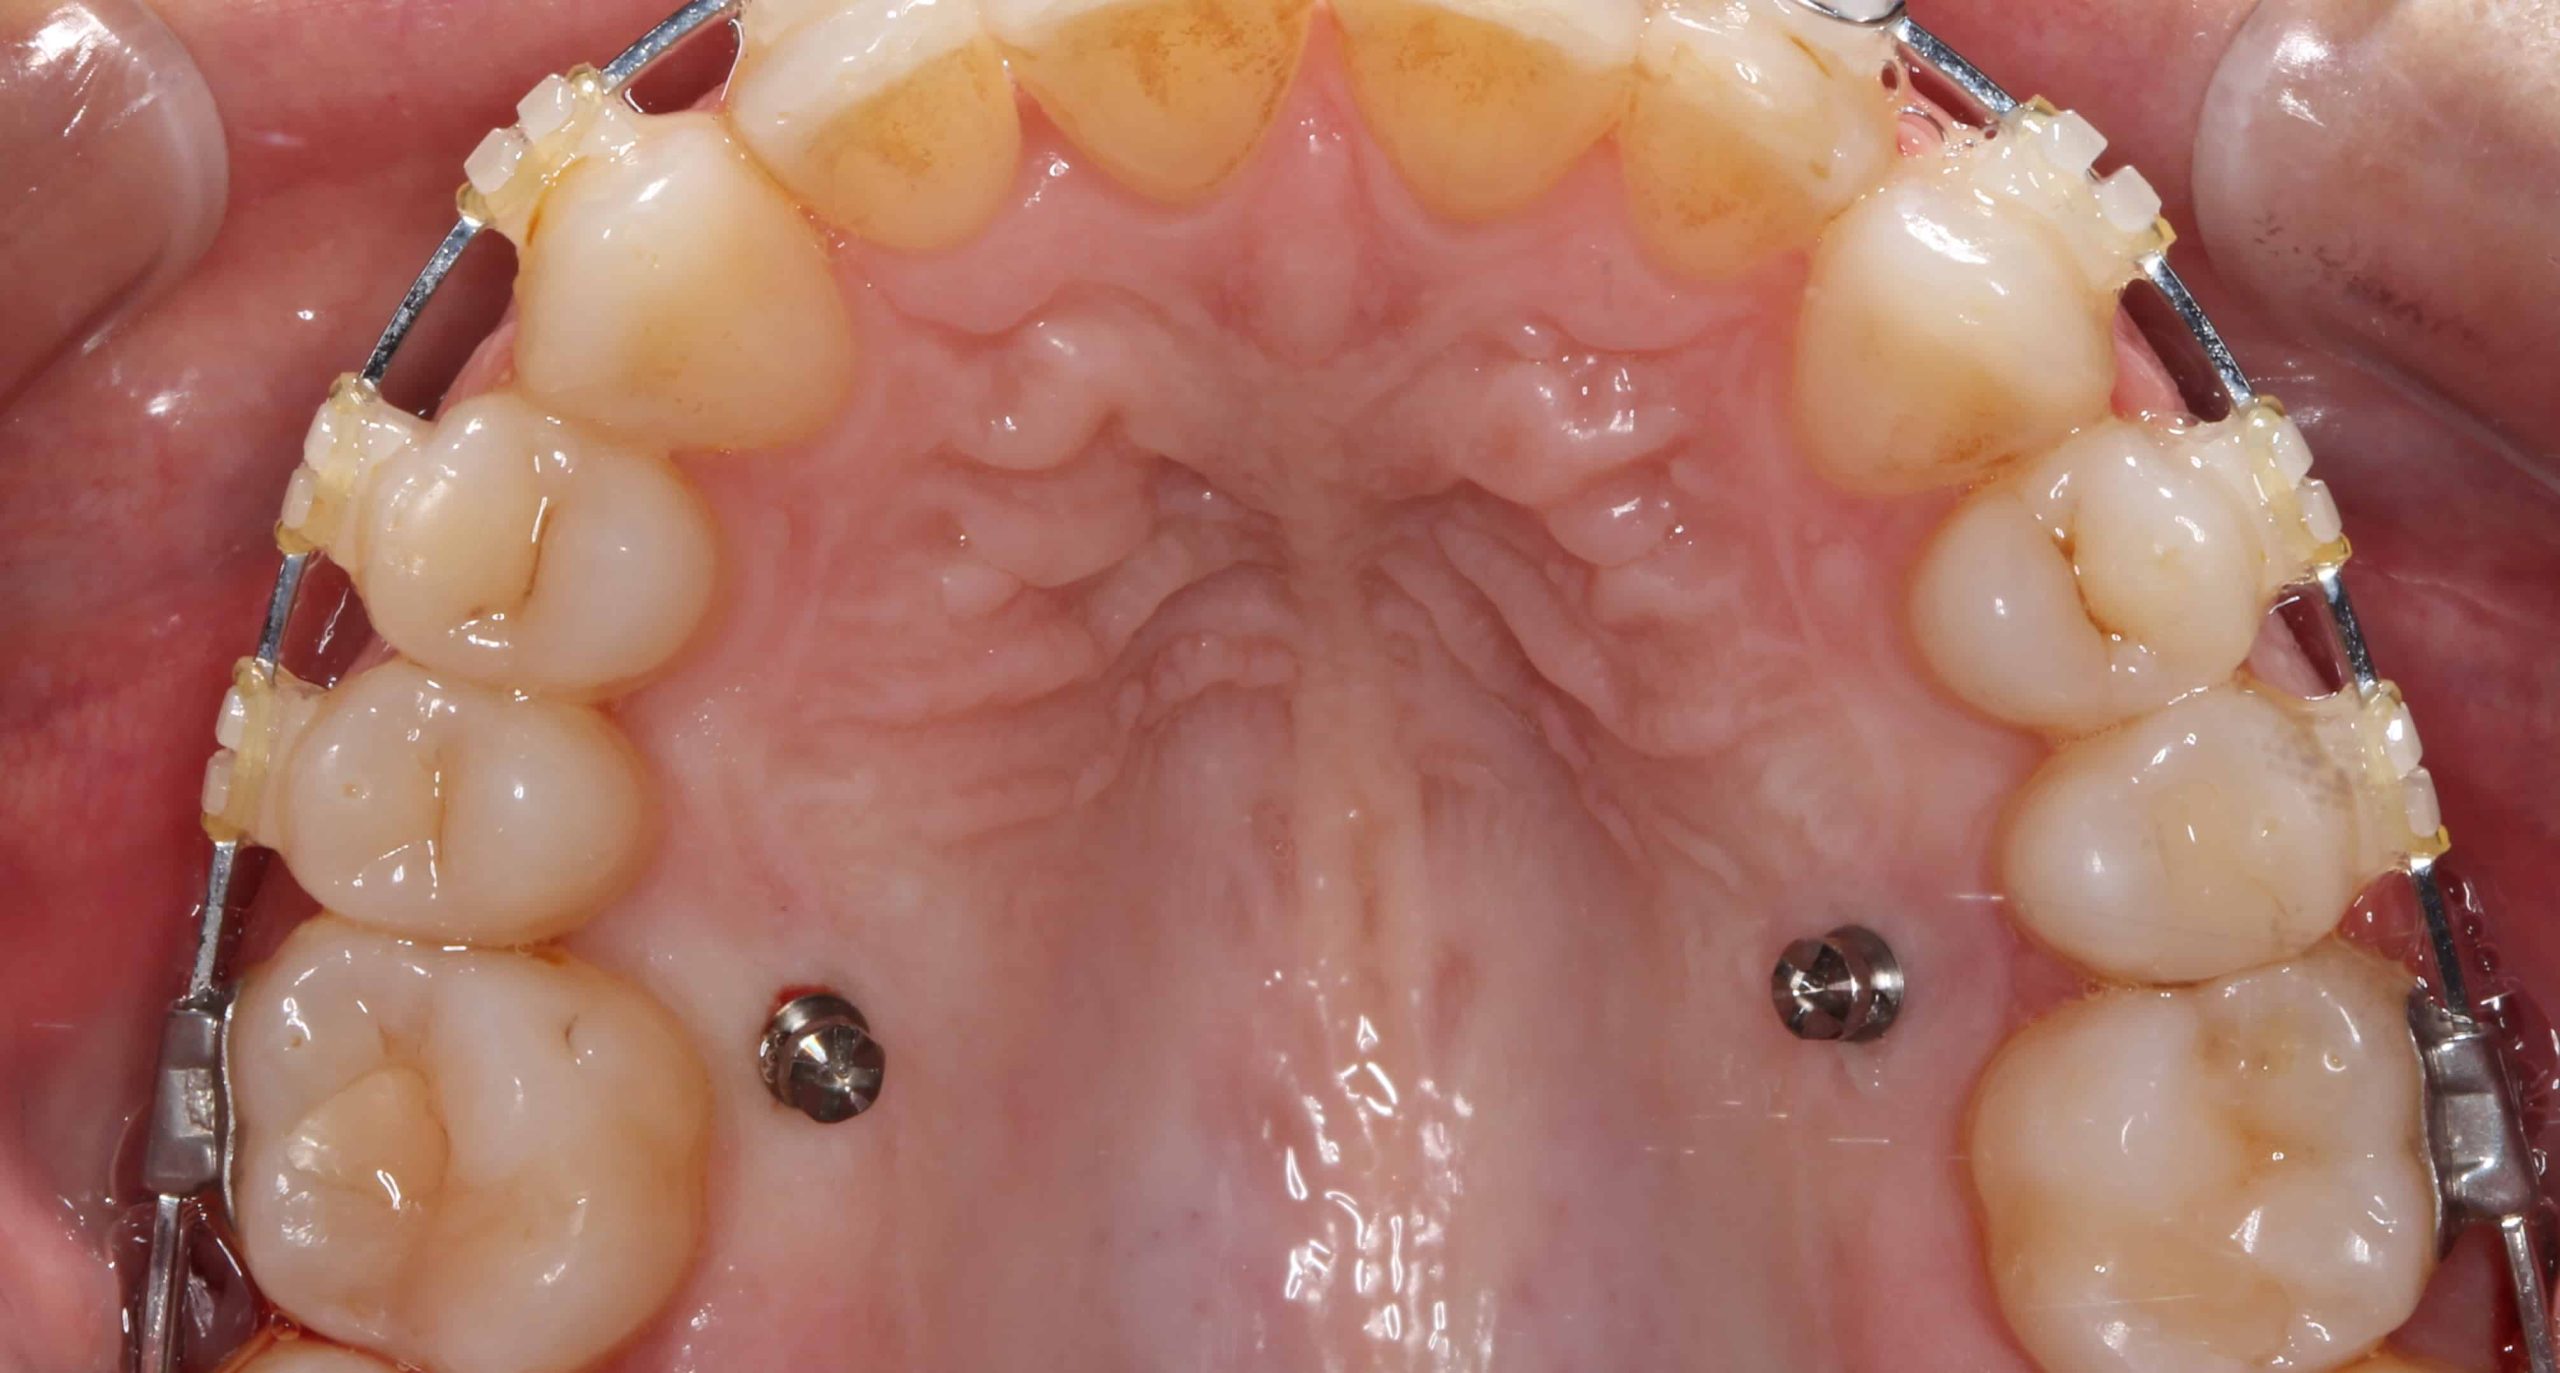

¿QUÉ SON LOS MICROTONILLOS DE ORTODONCIA?

Los microtornillos de ortodoncia no son lo mismo que los implantes dentales. Son unos pequeños tornillos de dimensiones mucho menores (su longitud varía entre los 6-12 mm y s